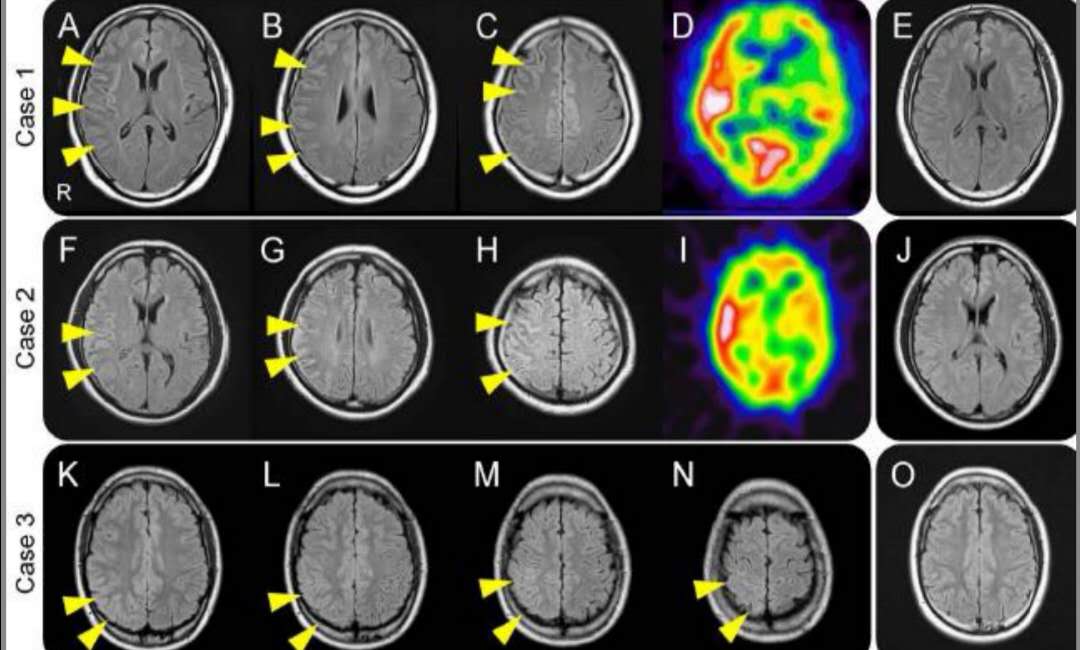

痛性眼肌麻痹综合征(tolosa-hunt综合征)临床及影像丨